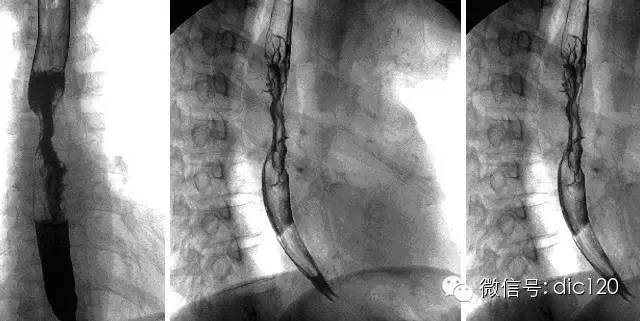

【病史臨床】男,63歲,胸痛,進行性吞咽困難伴消瘦20天。

【影像圖片】

【影像表現】 CT:表現現為食管壁明顯增厚,管腔狹窄;食管與周圍結構分界不清食管吞鋇:食管中段充盈缺損,管腔不規則狹窄,管壁僵硬,粘膜糾集破壞,與正常食管壁分界清晰。

【診斷】 病理診斷:食管(中下段)高-中分化鱗狀細胞癌,侵及食管壁全層。(圖1.2)